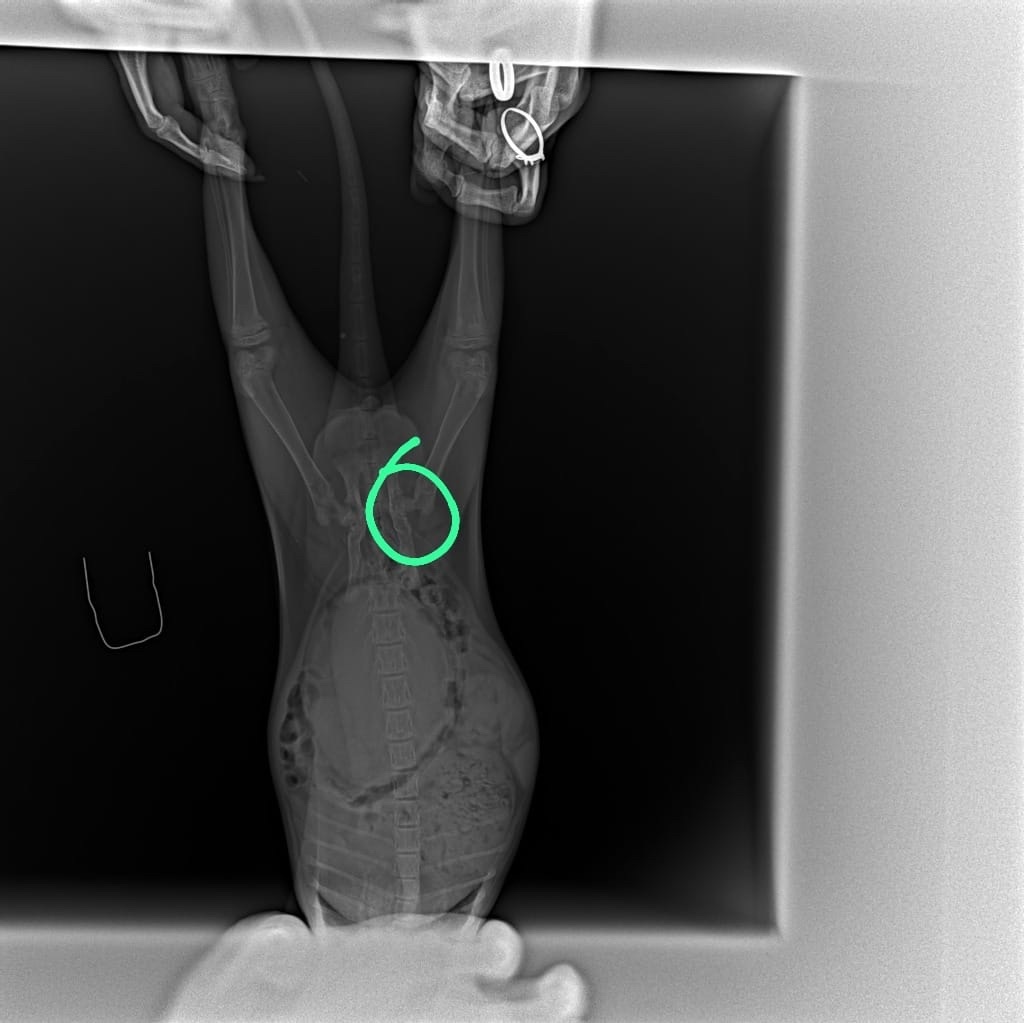

Однажды кто-то выбросил МЕСЯЧНОГО малыша на улицу… Котёнок был на столько мал, что не умел даже кушать самостоятельно. Но, на сей раз ему повезло, кроха был обнаружен семьей, которая и выкормила его. К сожалению, спасутся время, произошла tрагедия… Коненок залез в диван, им и был придавлен. Теперь малыш в приюте, так как лечить его денег у семьи НЕТ! У котёнка вторичный кормовой гиперпаратиреоз (рахит), в месячном возрасте отняли от матери и кормили молоком и мясом… Два переLома, оба по типу "зелёной ветки"...

Пeрелом шейки бедра левой тазовой конечности (подобный переLом был у нашего Снежка), второй переLом голени той же левой тазовой конечности! Все, что мы смогли, это сделать рентгены! Дальше НЕОБХОДИМ прием хирурга, лекарства, операция видимо, раз переLомы и спец корм. Так же АНАЛИЗЫ. Каждый день мы смотрим на этого малыша и понимаем, что время работает против нас! Ее глаза полны сtраха и ожидания, а мы бессильны помочь так, как он этого заслуживает. У ПРИЮТА НЕТ ДЕНЕГ, НЕТ ВРАЧЕЙ, НЕТ НЕОБХОДИМЫХ ЛЕКАРСТВ и опер стоит дорого! Мы ведь частный приют, где и так 500 животных…